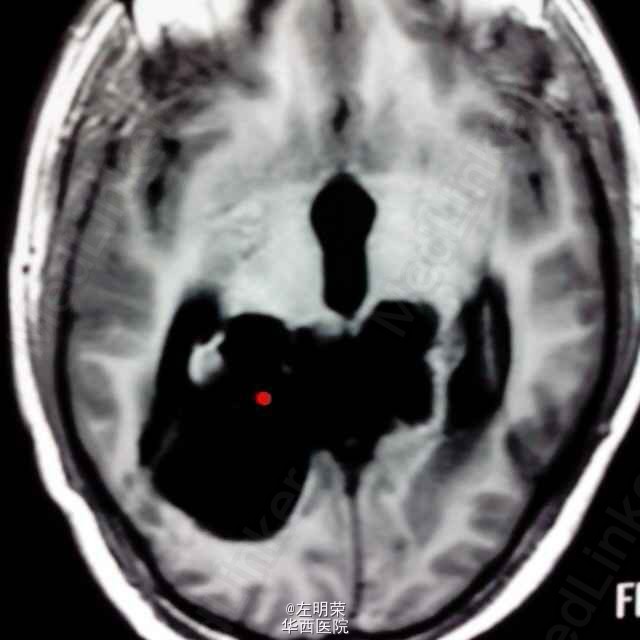

中年男性患者,“反复头痛一年”入院。查体未见明显异常;头部MRI示:松果体区占位,梗阻性脑积水。术中见病变位于右侧脑室三角区,病变范围广泛,侵及丘脑,脑干背侧,松果体区,呈白色珍珠状,质脆,切除过程中出血少,有白色坚韧包膜,予以全切,患者术后恢复良好;病理结果:松果体区表皮样囊肿。